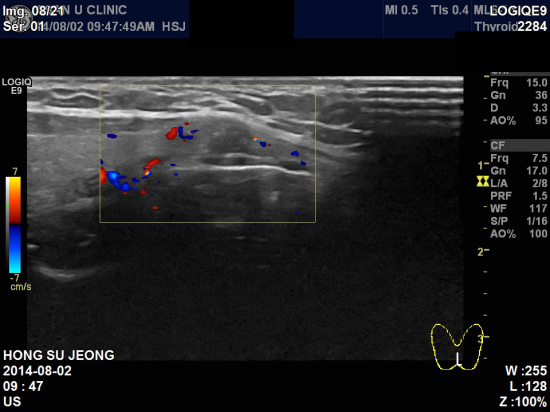

아산유외과 개원 후 24번째 갑상선암 진단.

좌측 목에 만져지는 멍우리로 내원하신 27세 여자분이십니다.

본원 갑상선 초음파상 양측 목의 림프절 비대 및

좌측에 1.2 cm 정도의 불분명한 결절 소견이 있었고,

세포검사 시행결과 갑상선 유두암으로 진단되셨습니다.

유방 뿐만 아니라 목 부근에도 만져지는 멍우리가 있을 시에는

지체하지 말고 바로 내원하여 전문의와 상담하시기 바랍니다.